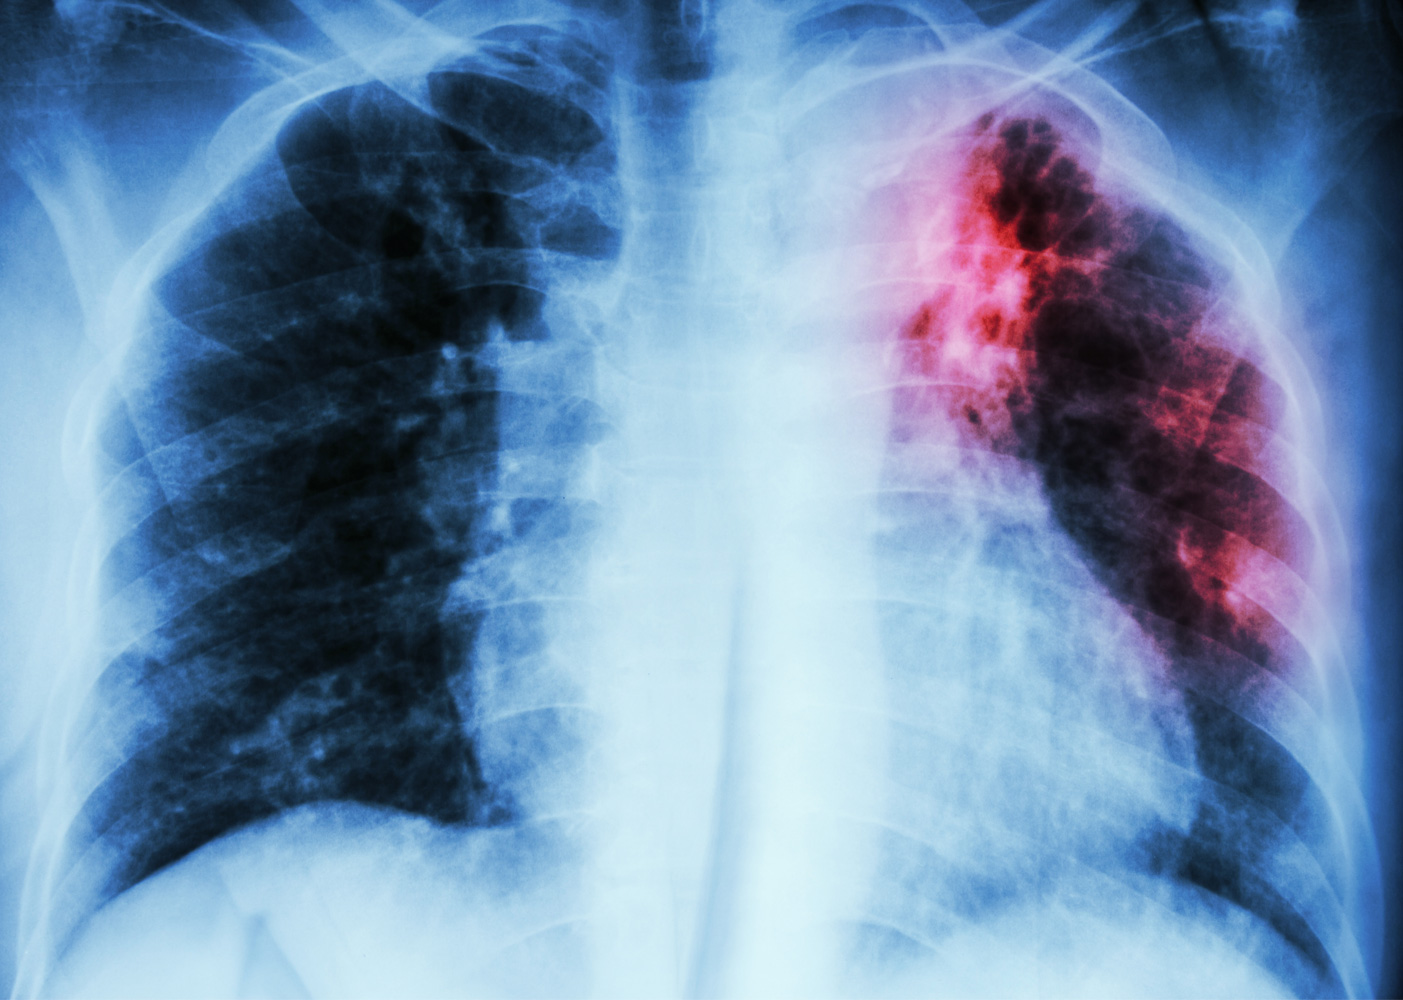

अपर मुख्य सचिव ने बताया कि प्रदेश सरकार ने पोर्टेबल, एआई-सक्षम हैंड हेल्ड एक्स-रे मशीनों का बड़े पैमाने पर विस्तार किया है, जिससे बिना लक्षण वाले टीबी रोगियों की पहचान संभव हो सकी है। इसके साथ ही राज्य में 930 नैट मशीनों के माध्यम से गुणवत्तापूर्ण जांच सेवाएं उपलब्ध कराई जा रही हैं। उन्होंने कहा कि टीबी मुक्त भारत अभियान के अंतर्गत 7 दिसंबर 2024 को देशभर में 100 दिवसीय सघन टीबी मुक्त भारत अभियान के प्रथम चरण की शुरुआत की गई थी, जिसमें उत्तर प्रदेश के प्रदर्शन को देखते हुए भारत सरकार ने राज्य को सम्मानित भी किया है।

अभियान की प्रगति पर प्रकाश डालते हुए अमित घोष ने बताया कि 7 दिसंबर 2024 से 17 जनवरी 2026 के बीच प्रदेश में 3.02 करोड़ जोखिम वाली (वलनरेबल) आबादी की स्क्रीनिंग की गई। जांच सेवाओं के विस्तार के तहत 81.29 लाख लोगों के एक्स-रे किए गए, जबकि 24.79 लाख नैट परीक्षण संपन्न हुए, जिससे समय पर और सटीक निदान सुनिश्चित किया जा सका।

इस व्यापक स्क्रीनिंग अभियान के परिणामस्वरूप राज्य में 7.33 लाख टीबी रोगियों की पहचान हुई। इनमें लगभग 1.69 लाख ऐसे मरीज शामिल हैं, जिनमें बीमारी के कोई स्पष्ट लक्षण नहीं थे। यह प्रोएक्टिव स्क्रीनिंग और आधुनिक डायग्नोस्टिक तकनीकों की प्रभावशीलता को दर्शाता है। राष्ट्रीय स्वास्थ्य मिशन की मिशन निदेशक डॉ. पिंकी ने बताया कि वर्ष 2015 की तुलना में प्रदेश में टीबी के नए रोगियों की दर में 17 प्रतिशत की कमी दर्ज की गई है।